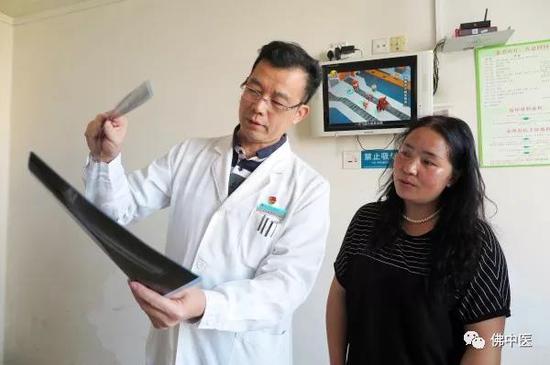

郭跃明主任向才巴母亲冬梅讲解病情